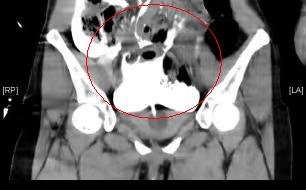

CT显示腹腔盆腔内大量积液(尿液),膀胱造影尿液混杂着造影剂,在盆腔、腹腔都显影出白色

经过膀胱造影CT检查,张迪确诊为腹膜内型膀胱破裂,腹腔内已有大量尿液,所以才引起腹膜炎刺激性腹痛等症状。一经确诊,医院立即开启绿色通道,对张迪紧急实施了剖腹探查、膀胱破裂修补术。患者手术顺利,术后患者需要留置导尿管一段时间,继续抗感染治疗,预防腹腔和盆腔脓肿形成,等待膀胱裂口愈合。